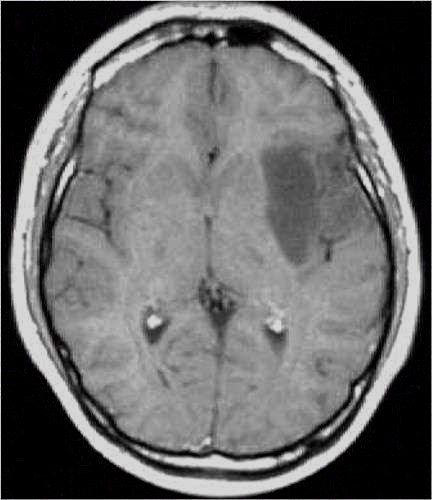

RM preoperatoria

RM

postoperatoria